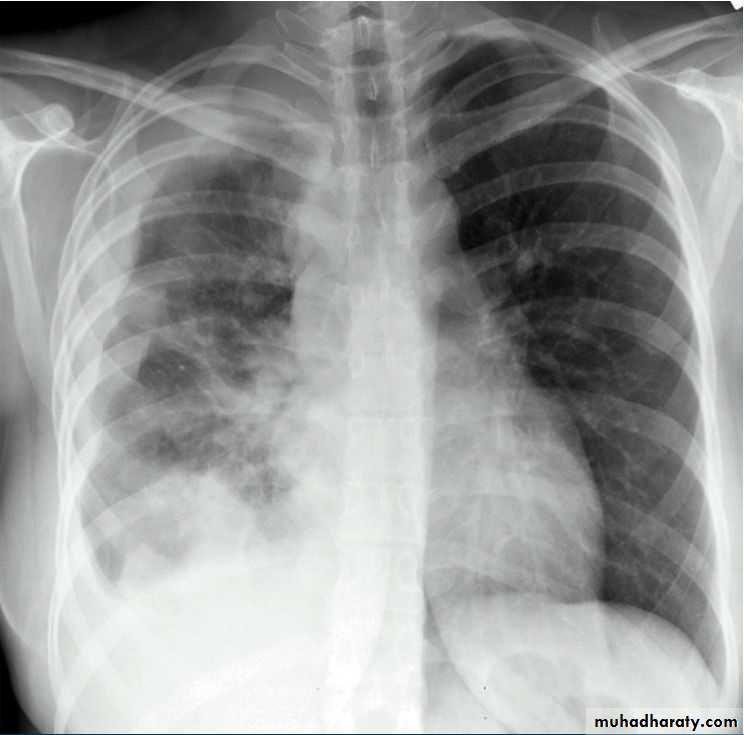

History; too shy to take of his shirt in the pool!